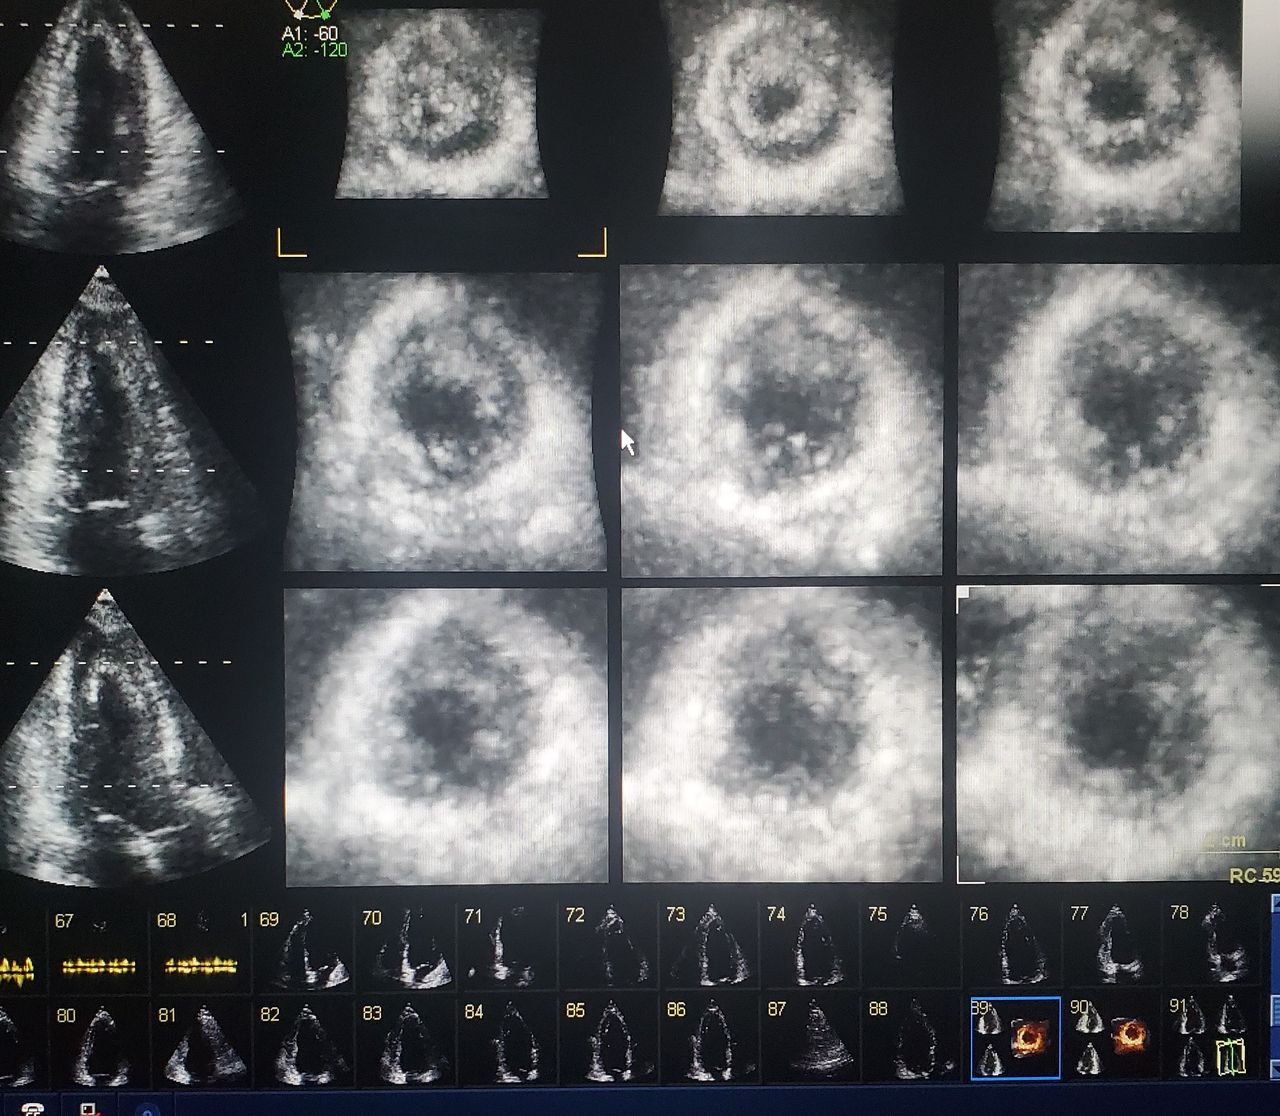

Adiestramiento en ecocardiografia( ultrasonido del corázón) en pacientes con cáncer .Utilizando técnicas avanzadas de mecánica ventricular. Donde se diagnóstica los efectos del tratamiento del cáncer en el corazón desde etapas muy tempranas antes de que se presenten los sintomas y se pueda otorgar tratamiento preventivo para cuidar el corazón.

Ecocardiograma transtoracico con el mejor equipo de la región

• Ecocardiografía